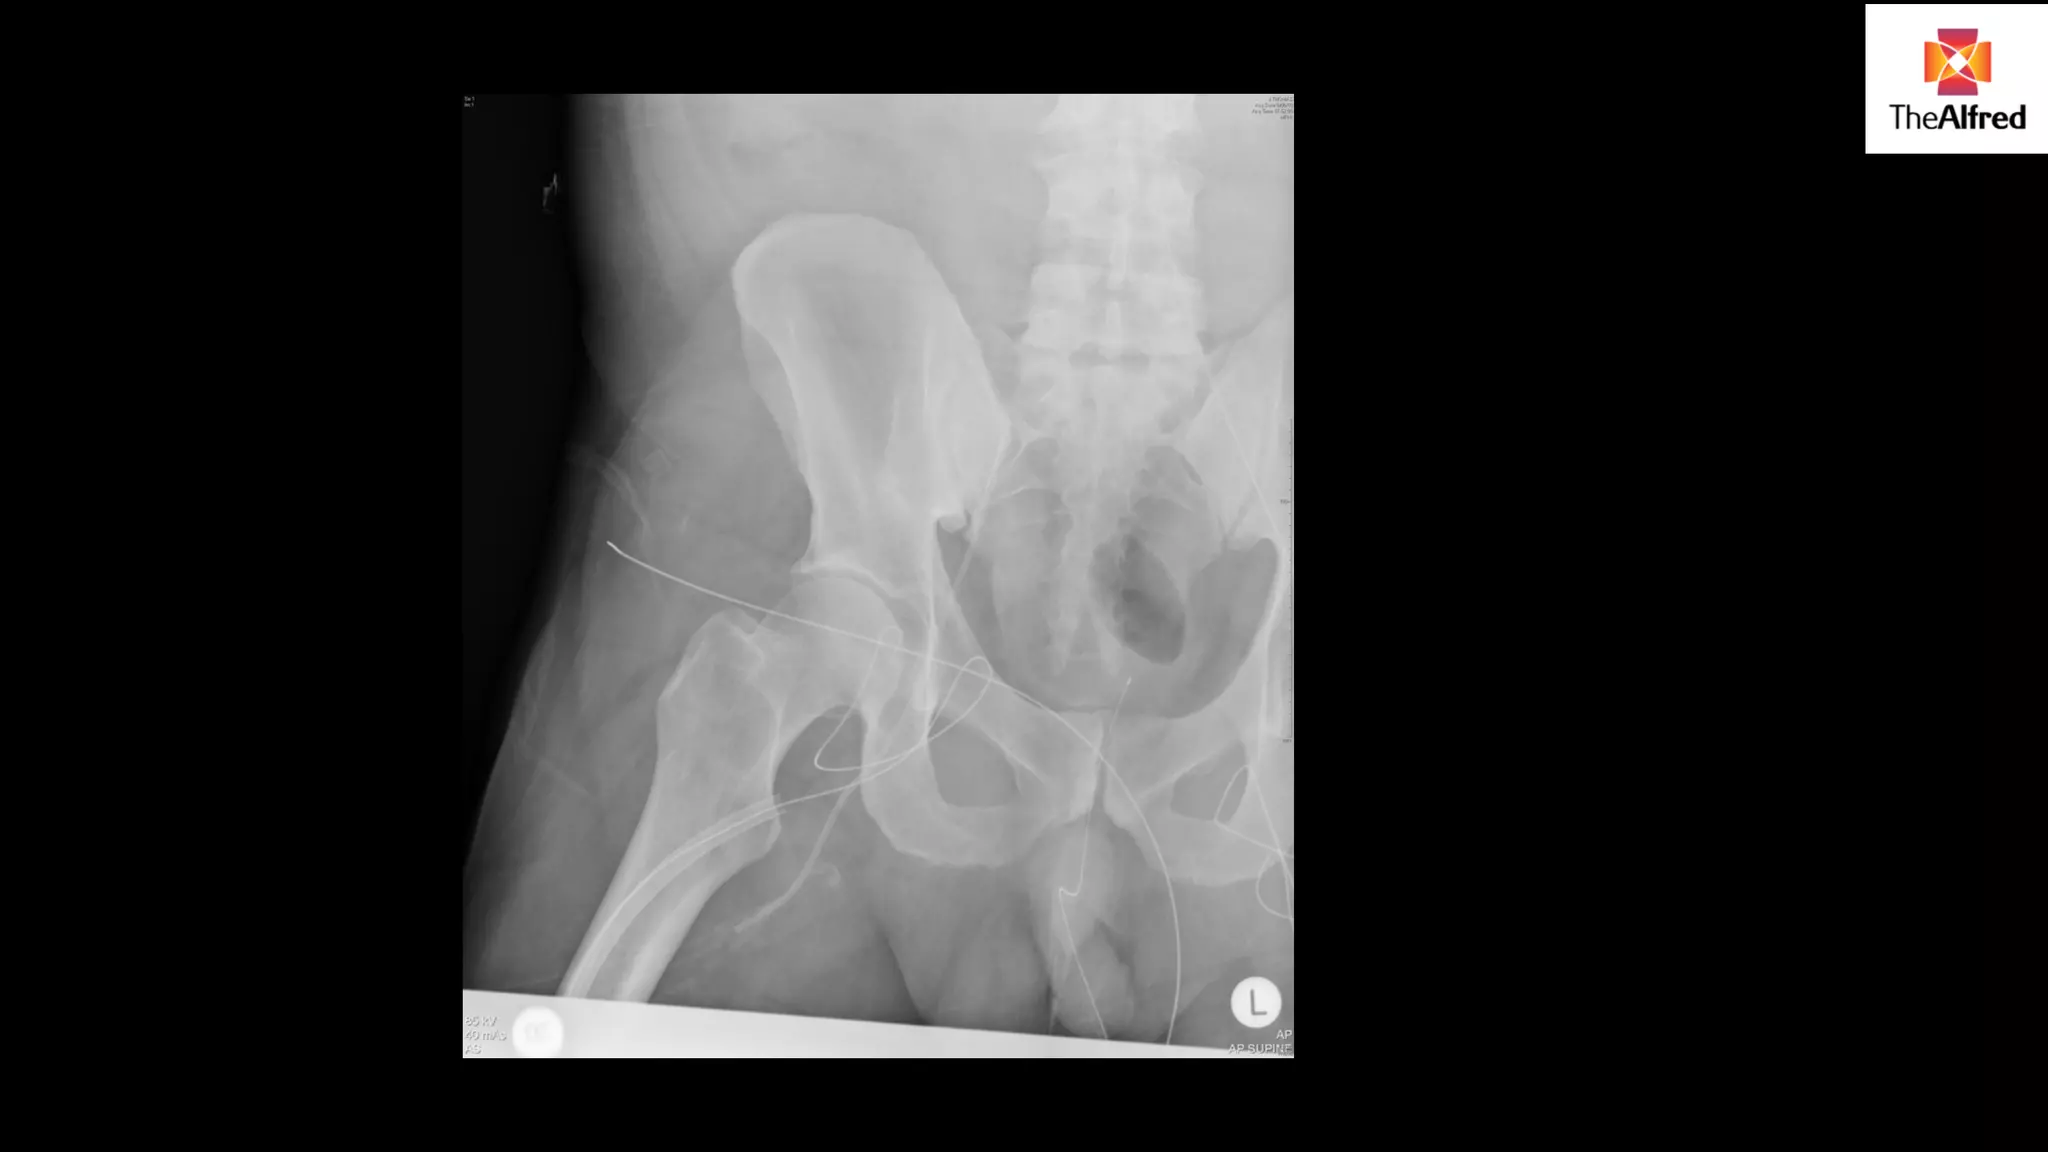

POST CANNULATION

High pressures in ECMO circuit

limiting support

Ultrasound of cannulas- in vessels

Venous cannula appropriately

placed

FURTHER TESTS?

abdo X ray